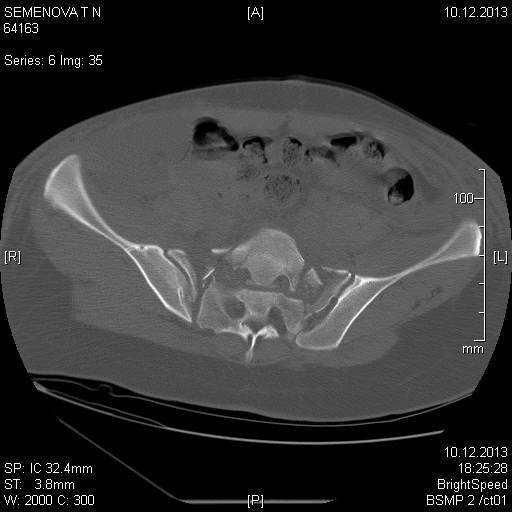

Доброго времени суток коллеги! Прошу вас, подсказать тактику в решении

оперативного лечения следующего сложного повреждения таза. Был ли опыт в

фиксации подобных повреждений?

Травма 03.12.2013,больная переведена из лечебного учреждения соседней

области. На данный момент у больной следующий диагноз: ЗЧМТ,сотрясение

головного мозга;Закр. травма грудной клетки,множественные переломы ребер

справа с повреждением ткани легкого, правосторонний гемопневмоторакс,

состояние после торакоцентеза; Закр.травма живота,разрыв

селезенки,гемоперионеум, состояние после лапаротомиии спленэктомии;

Закр. оскольчатый перелом сред-верх\3 левой бедренной кости, состояние

после накостного металлостеосинтеза; Закр.поперечный переломовывих на

уровне S1S2, многооскольчатый перелом латеральных масс крестца с обеих

сторон,перелом обеих лонных и седалищных костей.

Перелом поперечных отростков L1,L2,L3,L4, L5 позвонка справа. ШОК 3ст.

Вкратце изложил диагноз.

В настоящее время состояние больной тяжелое. Первым этапом планируем

наложить АНФ (переднюю раму) После стабилизации состояния необходимо

будет выполнить фиксацию.

Имеется один вопрос - какие импланты необходимы т.е. в какой комбинации

и какая последовательность фиксации?